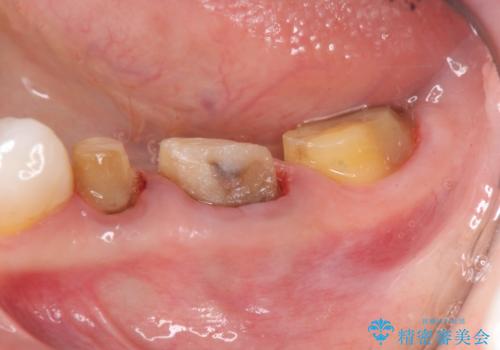

クラウン治療を行う場合歯ぐきの腫れが、クラウン製作の精密さにおいて問題点となることがあります。

このような場合、歯周外科を行うことでクラウン周囲の歯茎の状態を整備し精度に優れる治療を行うことができます。